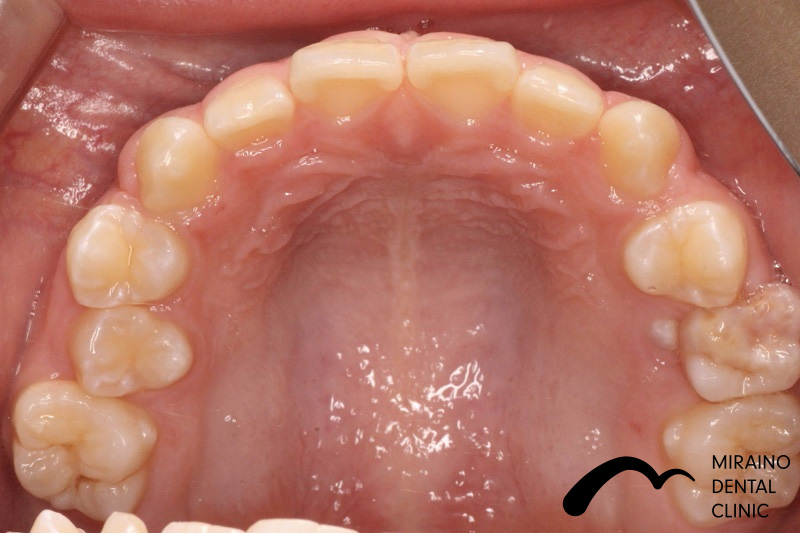

叢生(ガチャガチャ・ガチャ歯)②

| 施術名 | マウスピース矯正(インビザライン) |

| 施術の内容 | 歯科矯正でも目立ちにくい新しい矯正方法です。 透明に近いマウスピース型の矯正装置(アライナー)のため、歯に装着しても目立つことなく歯並びを矯正することが出来ます。 また、一人ひとりの合わせて矯正装置を作製いたします |

| 治療費 | インビザライン990,000円 |

| 考えられるリスク、副作用 | 疼痛・咬合時痛を生じる事があります。時間経過とともに治ります。 |

| 考えられるリスク、副作用[矯正] | 継続使用により緩んだり、外れやすくなる事があります。 割れたり壊れたりする事があります。 諸々の事情により、治療期間が当初よりも伸びる事があります。 所定の装着時間22時間を守って頂けない場合、治療計画どおりに治らない可能性があります。 歯が動く際に、痛みが出る事があります。 矯正期間中は虫歯や歯周病のリスクが高まりますので、しっかりとしたケアが必要です。 歯の移動に伴う歯肉退縮や歯根吸収が起こる事があります。 インビザライン・システム(invisalignR)は、アメリカのアラインテクノロジー社より提供されている、カスタムメイドの矯正装置ならびに、これを用いた治療システムを指します。 インビザラインを用いた治療は保険適用外の自由診療となります。 厚労省の認可(医薬品医療機器等法上の承認)は得ていないため、まだ明らかになっていないリスクが存在する可能性があることをご了承ください。 |

| 全て | 必ずしもご希望通りの見た目にならない事があります。 |